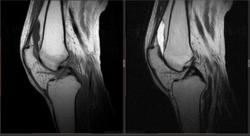

Мужчина 1963 г.р. Жалуется на боль в левом коленном суставе около 6 мес, в последний месяц стало совсем тяжко. Со слов заболел зимой, когда во время прогулки коленки сильно замерзли. Сам думаю на асептический некроз, но смущает множественность поражения.

Дмитрий, я в заболеваниях суставов не дока, но трабекулярный отек вкупе с выпотом может быть обусловлен воспалительными изменениями , но полностью начальные проявления аваскулярного некроза не могу отрицать.

я бы не поставил аваскулярный некроз. если исключена травма, дифференцировать с артритом.

Хрящ не поврежден, для артрита...